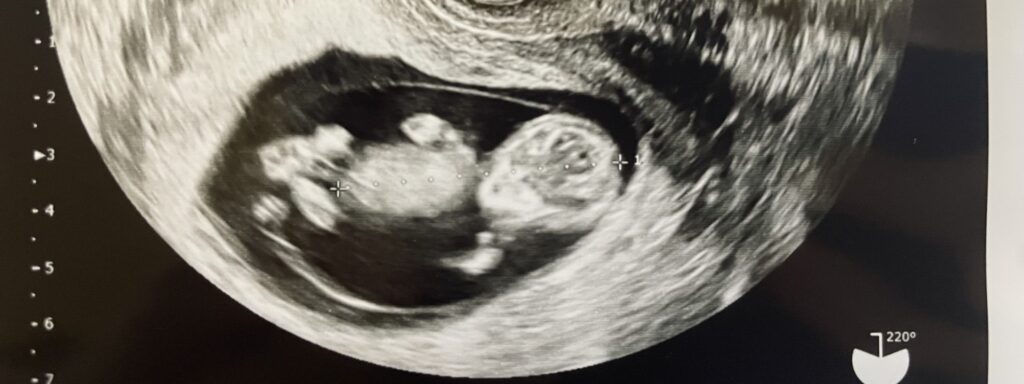

内診後は、そのまま経膣エコーで赤ちゃんの様子をチェックします😆

経膣エコーで赤ちゃんのチェック

この日も夫が付き添いでついてきてくれたので、一緒にエコーで赤ちゃんの様子を見ることができました!

流産なんかも気になる頃ですが、この日はエコーを入れた瞬間からめちゃくちゃ動き回っていて安心しました😌

しかも明らかに成長してて、手とか足の指までちゃんと見えました😳

まだ妊娠10週目なのに、こんなに成長するんですね!